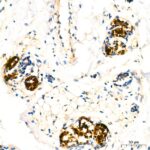

Immunohistochemistry analysis of paraffin-embedded human breast using Mammaglobin A Rabbit mAb (A19727) at dilution of 1:200 (40x lens).Perform high pressure antigen retrieval with 10 mM Tris/EDTA buffer pH 9.0 before commencing with IHC staining protocol.